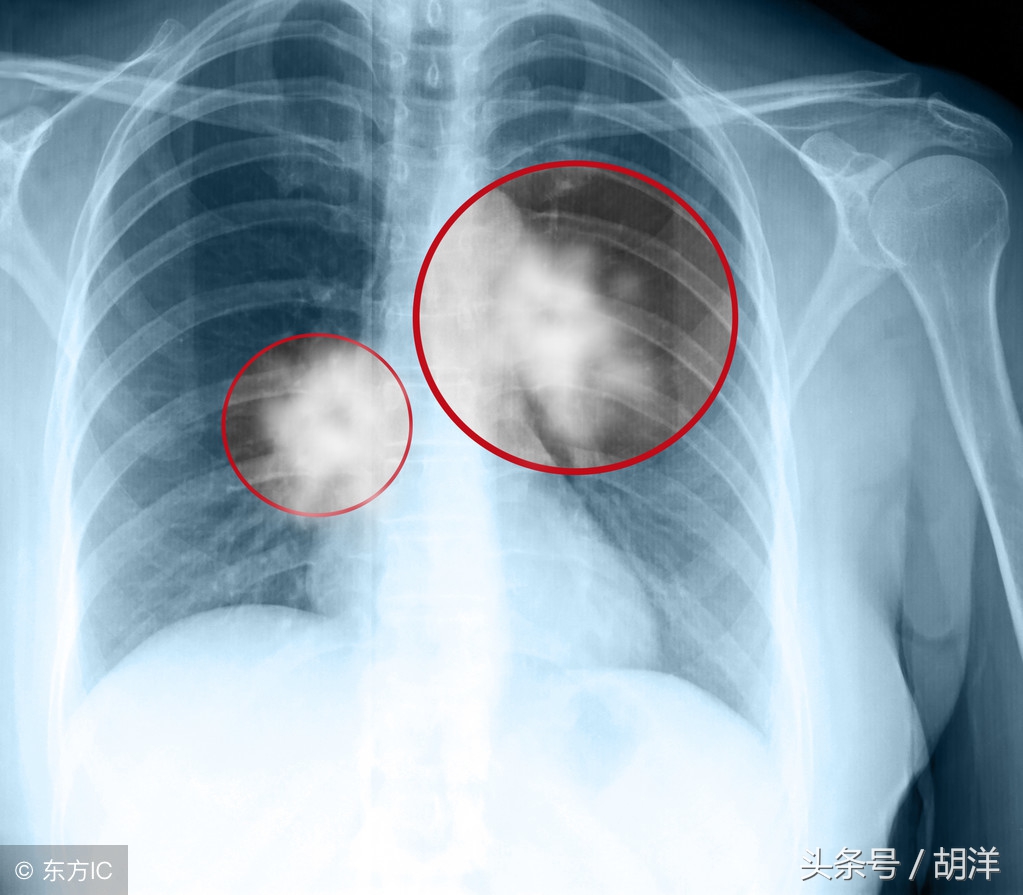

肺癌晚期了,家庭条件又不好,还有必要治疗吗?这个问题恐怕不同的人有不同的回答,不仅仅涉及到金钱的问题,还有亲情的因素。当生命即将结束,每个人都有强烈的求生欲望,绝大多数病人和家属都希望使用一切办法延长生命,也有少数家庭会因为意见分歧而反目成仇。

从年龄来讲,如果年龄很大,基础疾病多,体质不好,积极治疗的意义确实不大,但最基本的治疗,比如止痛、适当的营养治疗还是需要的。从疾病本身来讲,肺癌晚期并不意味着生命马上要终结,比如颈部淋巴结转移,纵隔淋巴结转移也是晚期,但短期内并不危及生命,这时候即便家庭条件不好,在体质允许的情况下还是需要做一些化疗或者放疗,尽量延缓疾病发展,现在大家都有医保,选用国产化疗药报销之后花费都不高。从经济的角度,如果家庭条件不好,肺癌晚期病人确实最好不要选择昂贵的进口药、靶向药和免疫治疗药物。人财两空、因病致贫是任何人包括医生都不愿意看到的结局,毕竟有限的金钱需要留一些给活着的人生活。从治疗效果来说,肺癌晚期治愈的机会微乎其微,这个每个人都是清楚的,但确实有部分幸运的病人寿命能延长很多年,临床上遇到过延长7-10年的病人,这其中印度靶向药和原料药起了一定的作用,所以如果条件不好,有基因突变的肺癌晚期病人可以试试印度版靶向药,过早的直接放弃治疗比较可惜。